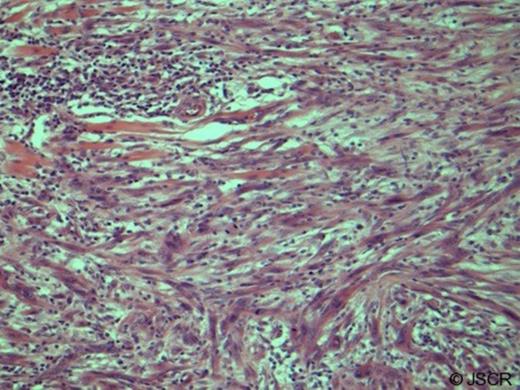

An 86 year old woman presented with a painful lump on her upper lip extending into the dome and floor of the nose. The lesion had apparently enlarged over 4 weeks extending through the lip into the floor of the nose. Investigations included, fine needle aspiration (FNA), CT and MRI. A diagnosis of MPNST was made based on histological examination of an incisional biopsy (Fig. 1).

Malignant peripheral nerve sheath tumour showing pleomorphic, mitotically active spindle cells infiltrating the dermis and muscles of facial expression (haematoxylin and eosin, original magnification x20 low power). Immunohistochemistry showed that the lesion was an Actin+ S-100+ neoplasm providing diagnosis of MPNST.